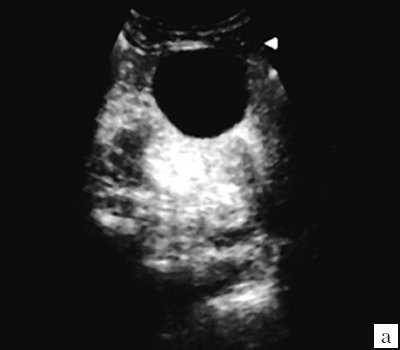

Первая категория - простая солитарная киста почки. При УЗИ простая киста почки представляется в виде эхонегативного образования округлой или овальной формы. Характерны отсутствие визуализации стенок и внутренних структур в образовании, четкие ровные непрерывные контуры. Возможно наличие эффекта дорсального усиления соответственно объему кисты (рис. 1).

а) Образование имеет округлую форму, четкие ровные контуры. Стенка не видна, внутренние структуры и перегородки отсутствуют.